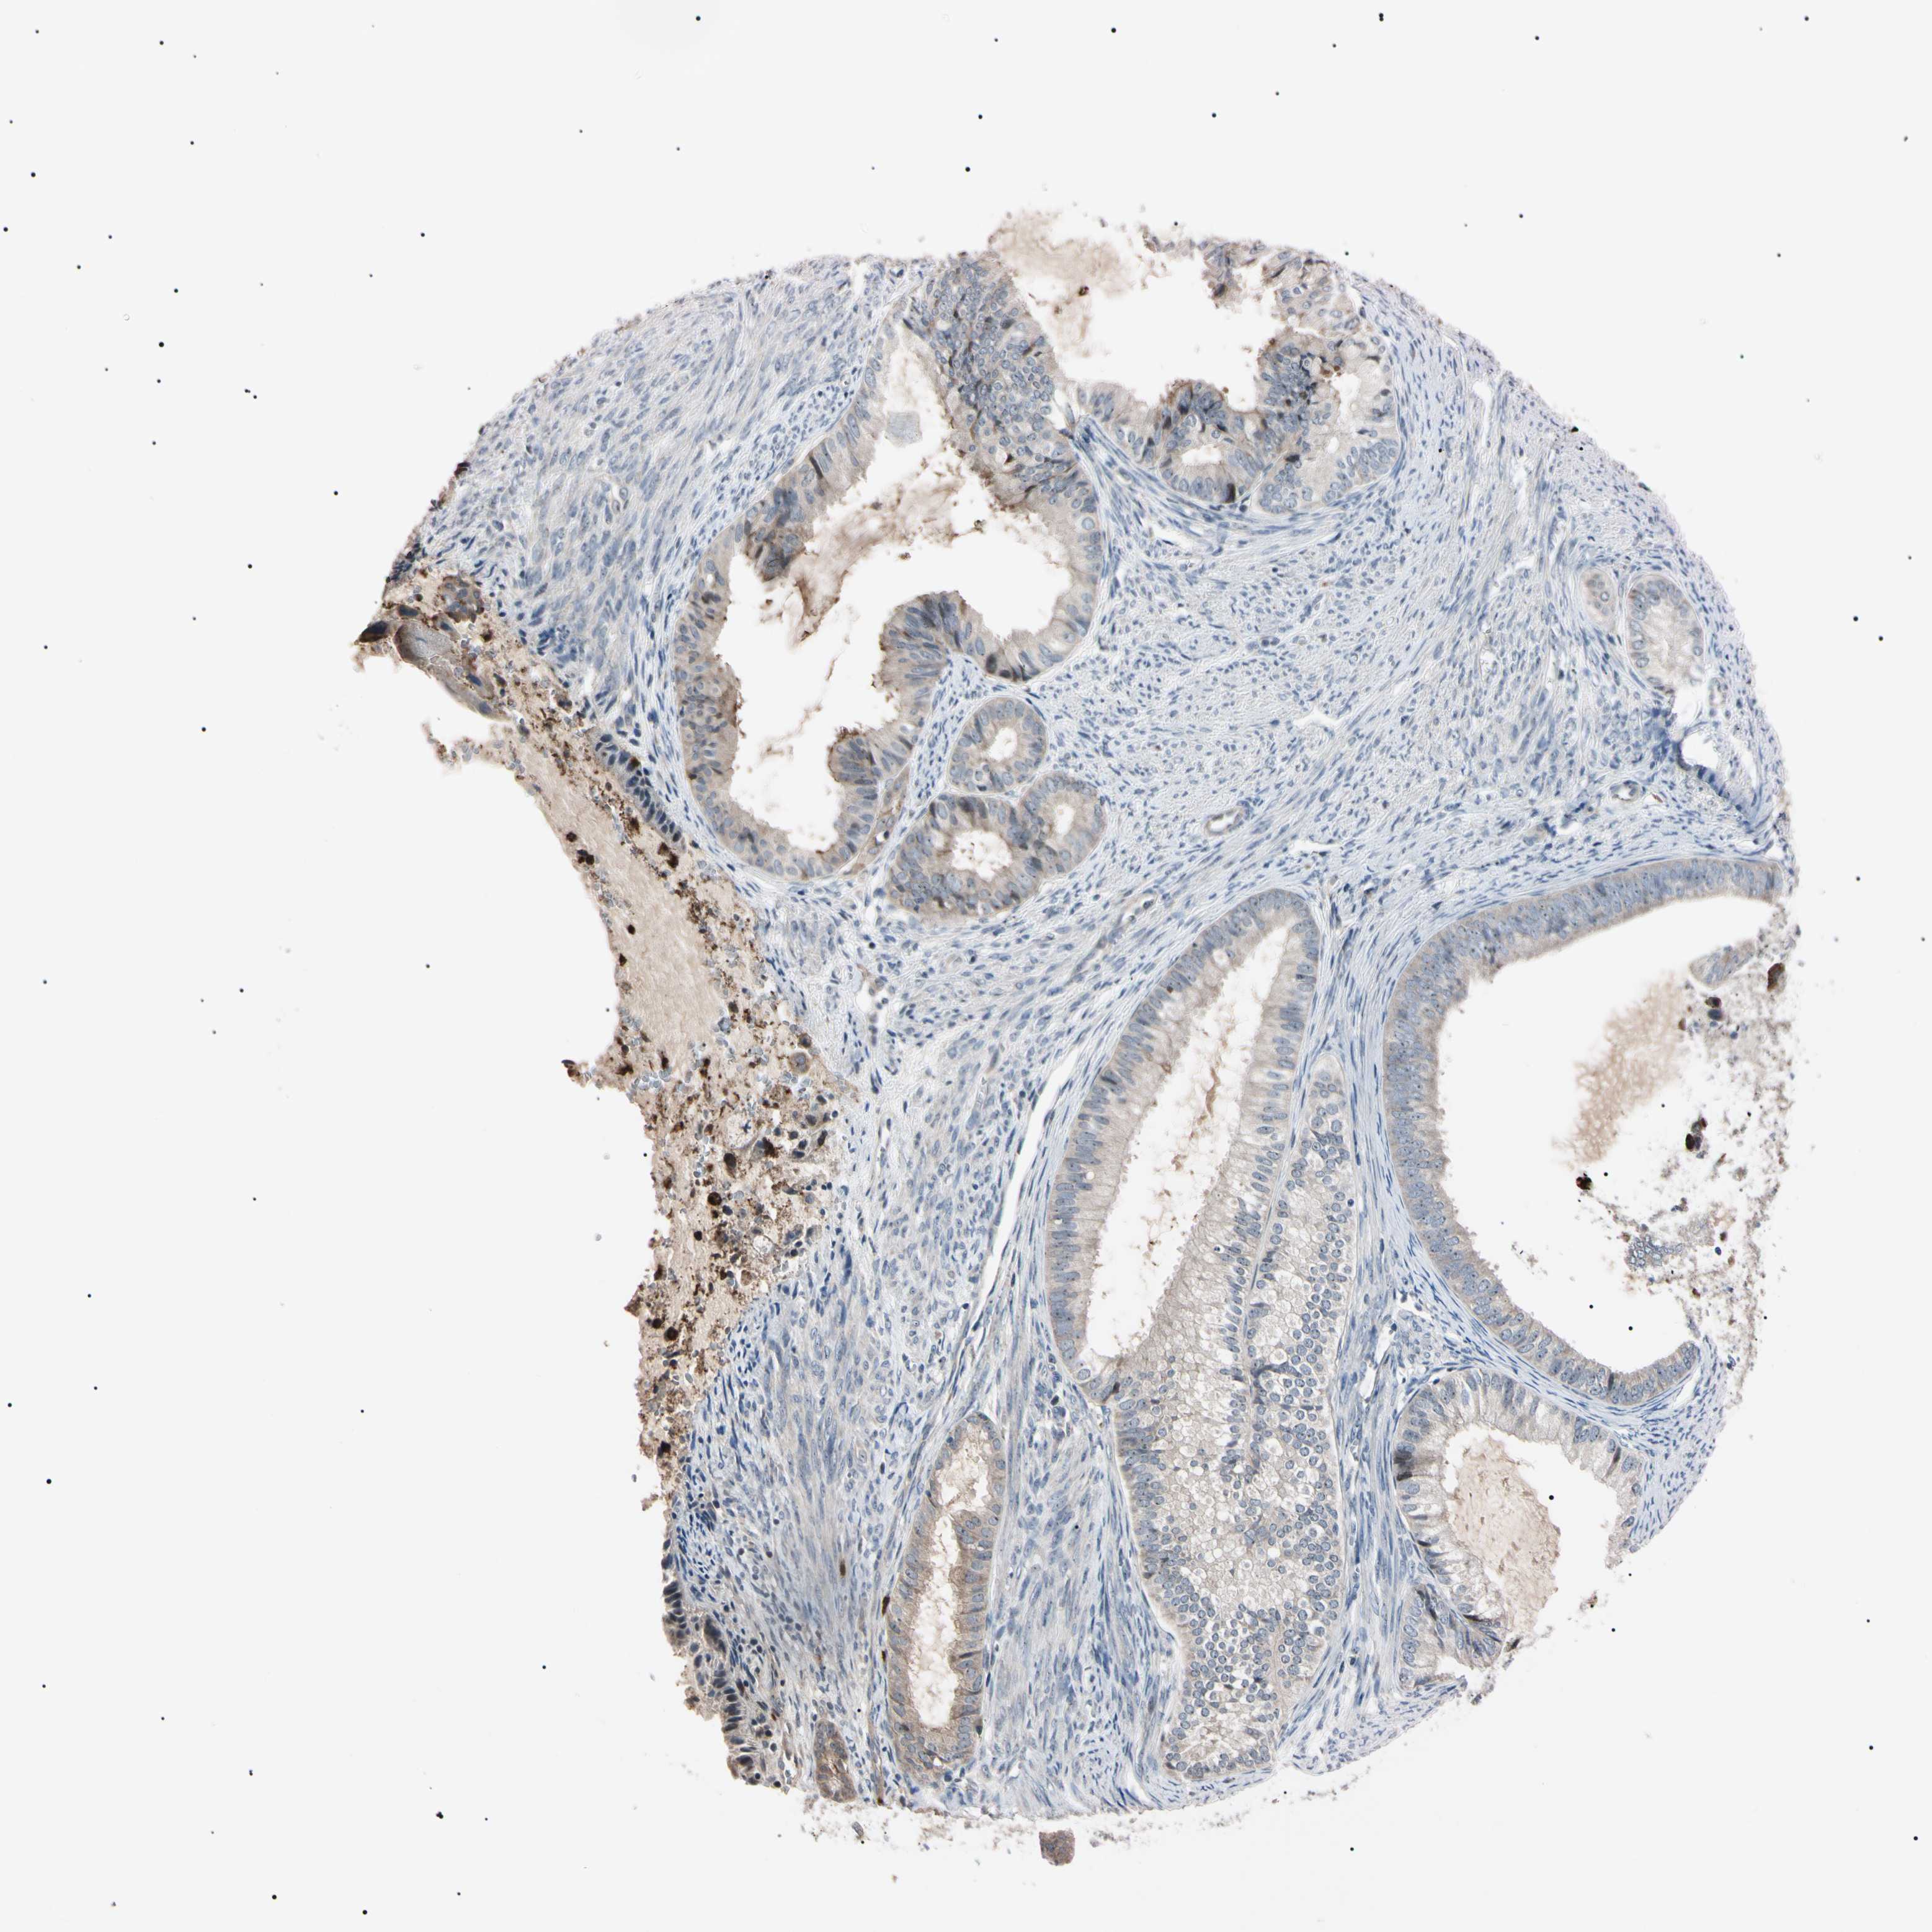

ENDOMETRIAL CANCER - Protein expressioni

A mouse-over function shows sample information and annotation data. Click on an image to view it in a full screen mode. Samples can be filtered based on level of antibody staining by selecting one or several of the following categories: high, medium, low and not detected. The assay and annotation is described here.

Note that samples used for immunohistochemistry by the Human Protein Atlas do not correspond to samples in the TCGA dataset.

Antibody stainingi

Antibody staining in the annotated cell types in the current human tissue is reported as not detected, low, medium, or high, based on conventional immunohistochemistry profiling in selected tissues. This score is based on the combination of the staining intensity and fraction of stained cells.

Each image is clickable and will lead to virtual microscopy that enables deeper exploration of all samples and also displays staining intensity scores, fraction scores and subcellular localization as well as patient and tissue information for each sample.

Antibody HPA008052

Antibody CAB010277

Staining

High

Medium

Low

Not detected

Intensity

Strong

Moderate

Weak

Negative

Quantity

>75%

75%-25%

<25%

None

Location

Nuclear

Cytoplasmic/membranous

Cytoplasmic/membranous,nuclear

Adenocarcinoma, NOS